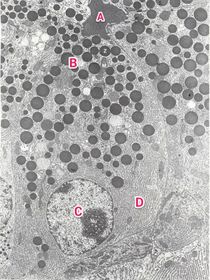

TEM OF Pancreatic acinar cell

A : Lumen B : Zymogen granules C : Nucleus With evident nucleolus D : rER